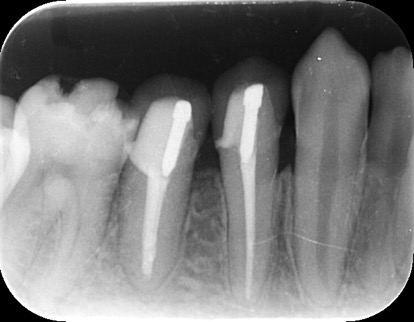

それは歯の先に枝分かれが多く存在し、そこにばい菌が入り込んで難治性となっているからです。ではその場合どうするのか?外科治療をします。その枝分かれの部分を切り落とすのです。今回はその前後のレントゲンの写真をお見せします。

| 根の中の薬が十分に充填されておらず、根の先が周りと比べて黒くなっており、炎症があると判断できます。 | 根の中にしっかりとお薬を緊密に充填しましたが、まだ根の先に黒くなっている部分があります。 |

| 根の先の黒い影は消失しました。 | 術後6ヶ月のCT画像です。こちらでも、根の先に黒い影は見当たらないです。 |

このように外科的治療で病変部を切除することでしっかりと治癒させることが可能です。根の治療は細菌との戦いです。難しいですが、やりがいがあります。